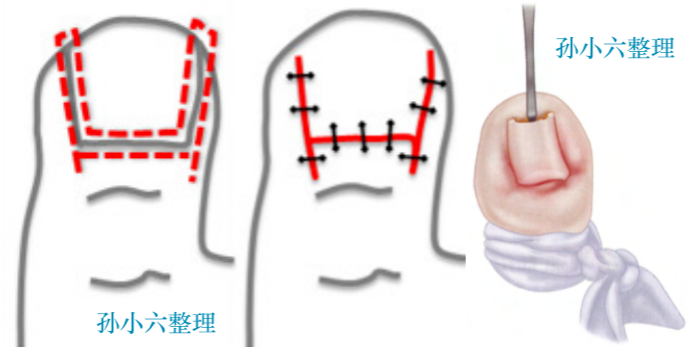

手术治疗

手术方法